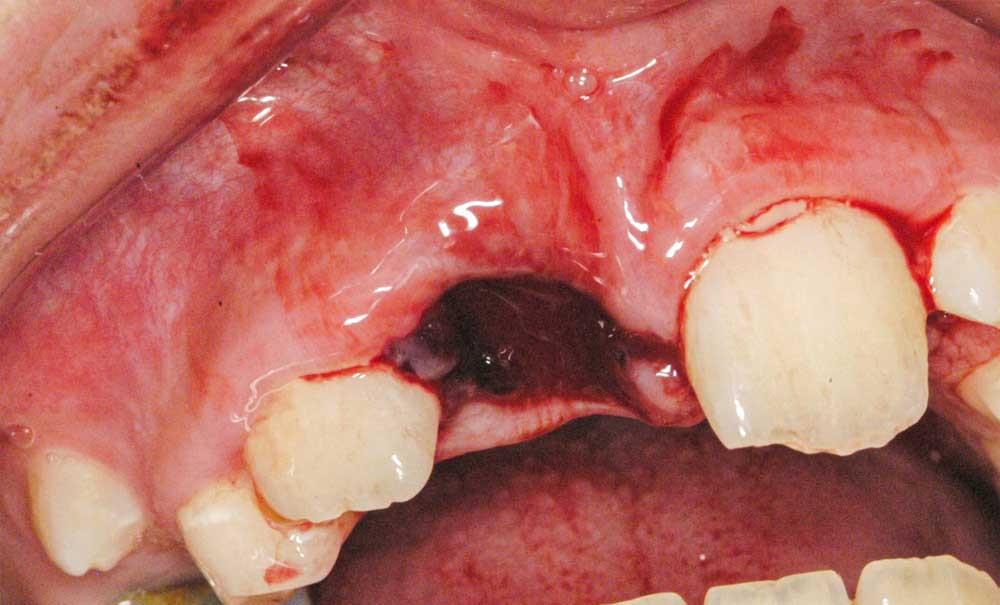

Enfant de 9 ans dont une incisive centrale maxillaire a été expulsée en jouant au football. Appel immédiat de la mère à qui l’on conseille de conserver la dent expulsée dans du sérum physiologique (fig. 1). Le temps extra-alvéolaire à sec a été inférieur à 5 minutes. Le patient arrive 40 minutes après le traumatisme dans l’Unité d’Odontologie pédiatrique. Après interrogatoire, examen clinique et radiographique, un rinçage de l’alvéole est effectué et la dent est réimplantée le plus rapidement possible (fig. 2). Une contention semi-rigide est ensuite placée (fig. 2). La dent étant mature, la prise en charge endodontique (séance de Ca(OH)2 puis obturation à la gutta percha) débute deux semaines plus tard (fig. 3 et 4) afin de limiter les risques d’infection, de résorption. Le suivi sur quatre années montre une dent fonctionnelle, sans ankylose ni résorption radiculaire ou osseuse.